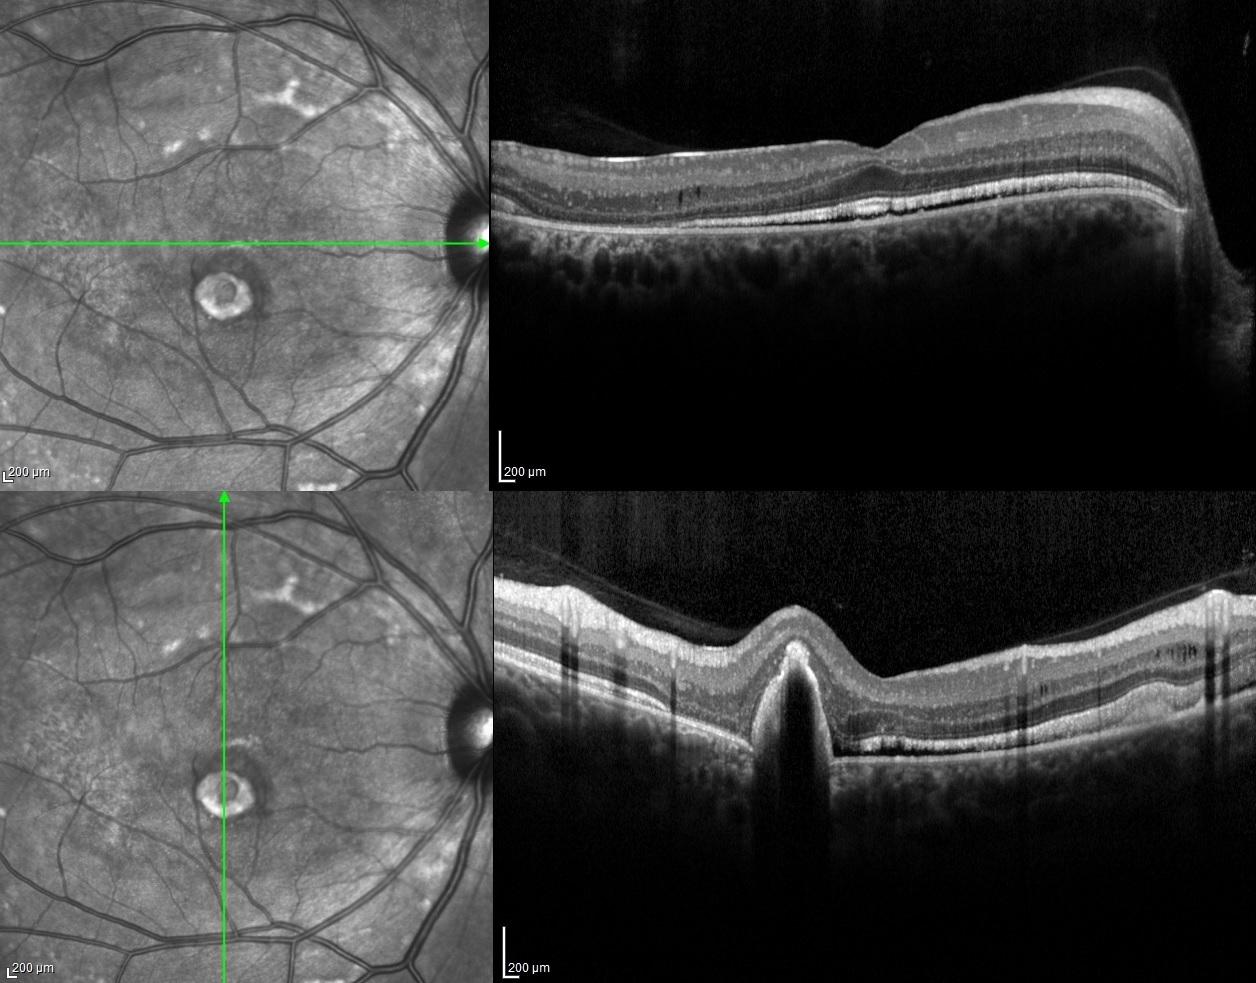

Spectral-domain optical coherence tomography of both eyes revealed minimally serous retinal detachment with dome shaped hyperreflective accumulation on RPE as well as retinoschisis in inner nuclear layers.